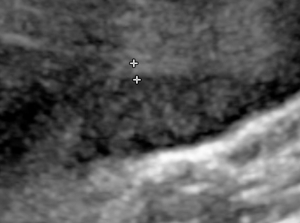

Florence Lam在朱凱婷建構的空間中渡過一晚,並視之為一個繭,既是孵化器,亦如庇護所。她帶來廿六個豆袋相伴,每個都標記着她一年光陰,直至一次墮胎的經歷重塑其人生。在她暫留期間,房間封閉,只允許觀眾透過屏障或攝影鏡頭見證。藝術家將自己月經來潮時的子宮超聲波掃描疊加在實時影像之上,交織時間的流逝與身體週期的循環。在展演中,藝術家重曝由內而生的主客角色,棲息於自己的生育器官,反覆休歇、創作和示意。